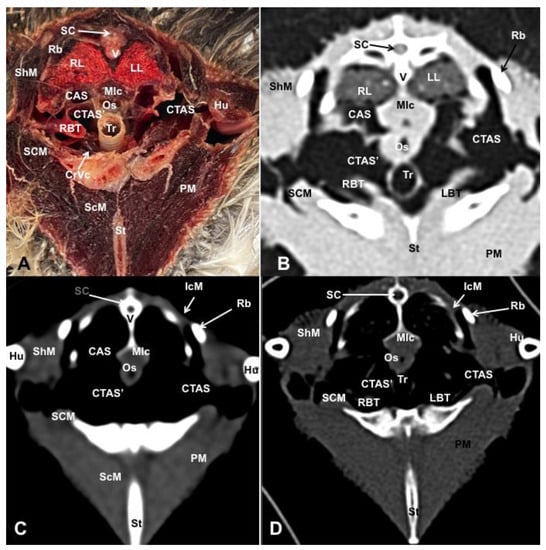

3. Results

3.1. Anatomical Dissections and Cross-Sections

3.2. Computed Tomography Images